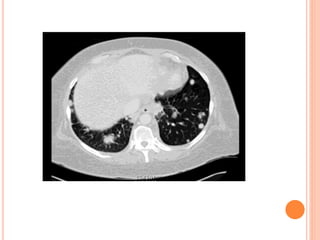

This document summarizes aspergillosis, including invasive pulmonary aspergillosis (IPA), chronic necrotizing aspergillosis (CNA), and aspergilloma. Aspergillus is a common mold that can cause a variety of pulmonary diseases. IPA predominantly affects immunocompromised patients and presents as pneumonia. Diagnosis involves tissue biopsy, galactomannan testing, and imaging. Voriconazole is recommended treatment. CNA occurs in patients with underlying lung disease and is characterized by slow lung tissue invasion. Itraconazole is effective treatment. Aspergilloma involves a fungus ball in a pre-existing lung cavity.